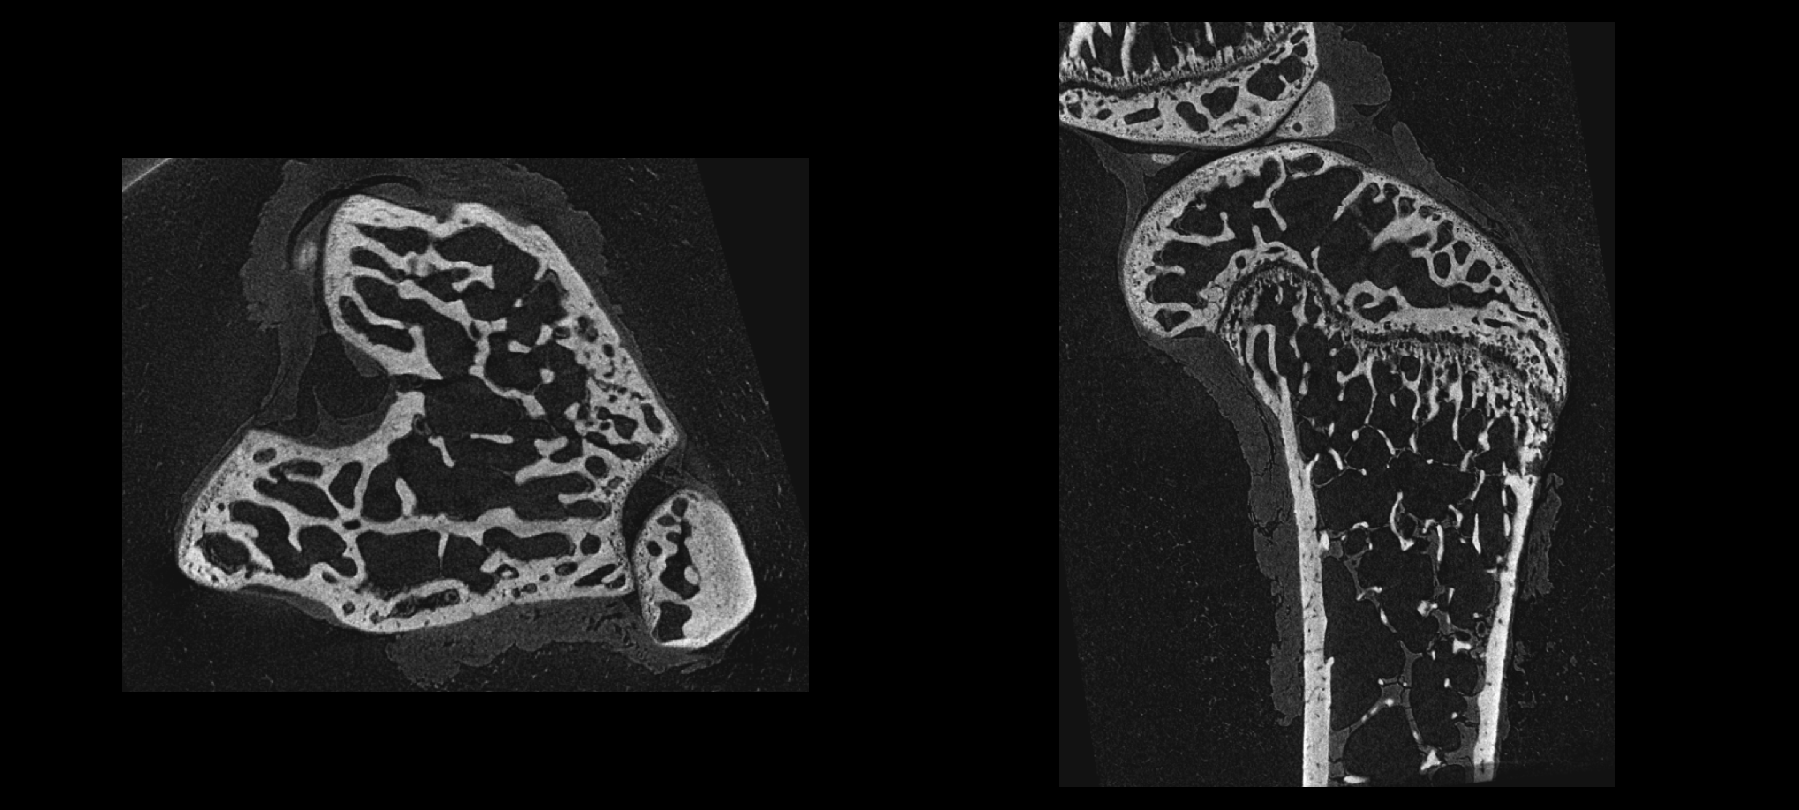

离体小鼠股骨扫描二维断层成像

IMAGING 100 软件系统中骨分析模块,具有自动分割皮质骨和骨小梁功能,可在图像上选择感兴趣区域(Region of interest,ROI)做阈值分割等操作,分割皮质骨和松质骨,分别提取不同组织区域,从而对皮质骨和松质骨的各种形态学特性进行研究和分析。

2D及3D骨小梁和皮质骨分割提取